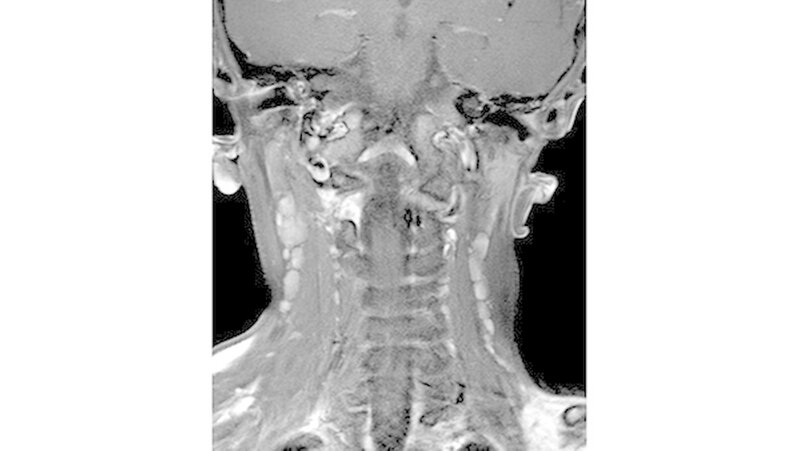

In der HR-CT zeigten sich Arrosionen am Oberkiefer und Kieferhöhlenboden sowie eine irreguläre Knochenbinnenstruktur mit Rarefizierung der Kochentrabekel und Demineralisation im Mittelgesichtsbereich, weiterhin eine Verschattung der Kieferhöhlen beidseits (Abbildungen 2 und 3).

Sonografisch fielen multiple pathologisch vergrößerte Lymphknoten am Hals beidseits auf. Dies bestätigte sich in der MRT, welche darüber hinaus eine Infiltration von Ober- und Unterkiefer, Schläfen- und Keilbein mit ossärer Destruktion und Knochen überschreitender Weichteilkomponente aufwies (Abbildung 4). Weitere Herde wurden im Schulterblatt, am Humerus-Kopf, sowie im Schlüsselbein, und an den Halswirbeln festgestellt.